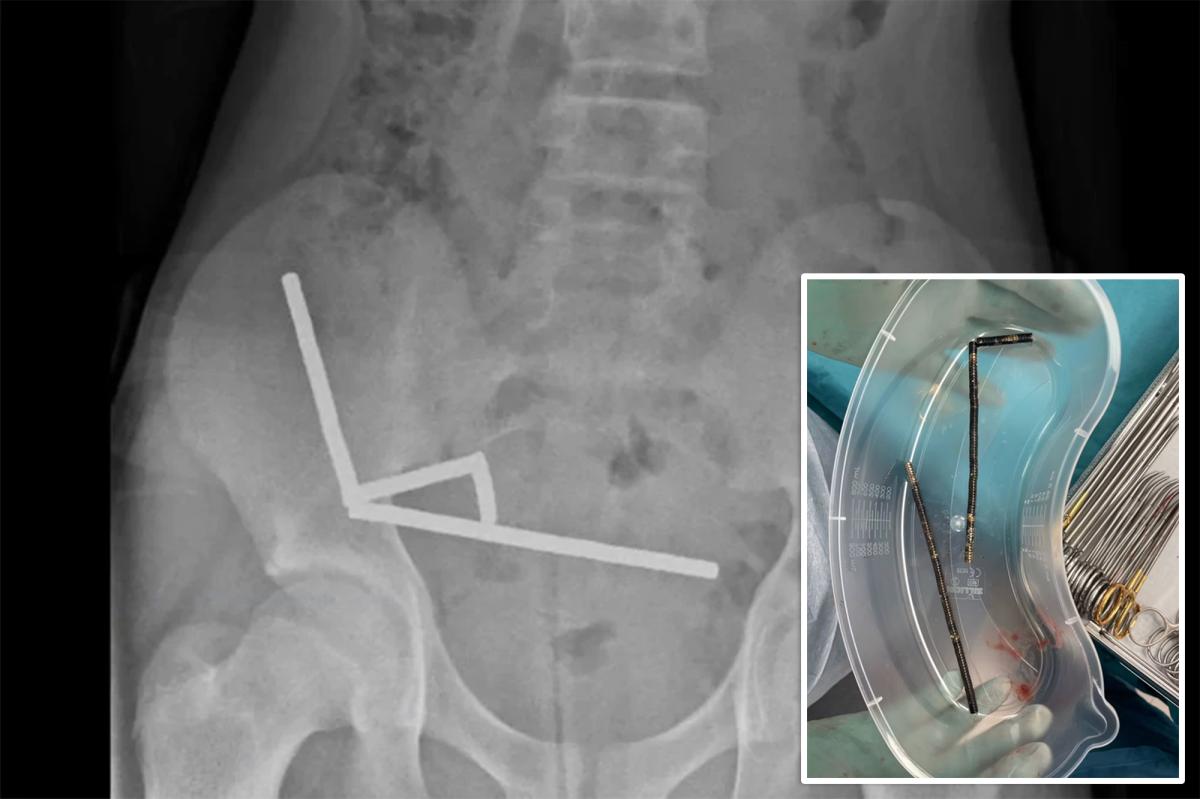

X-rays revealed four chains of magnets lodged in different sections of his intestines, pulling together and cutting off blood flow to nearby tissue.

Doctors said the magnets measured 5 by 2 millimeters each and had clumped into four straight lines inside the boy’s intestines. The magnetic pull caused sections of bowel to adhere together, effectively pinching the tissue between them.